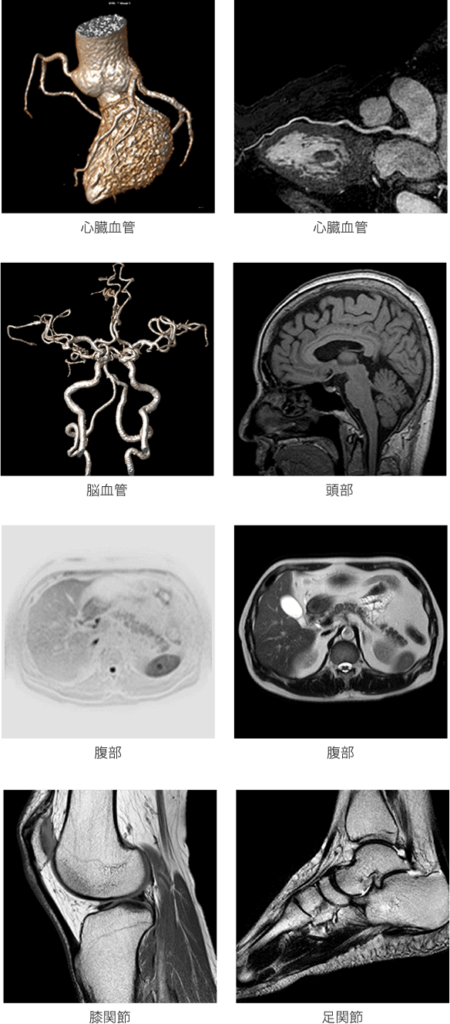

高分解能画像例

MRI検査は被曝がなく安全であり、微小な脳実質の病変だけでなく、微細な血管の状態を観察することができます。

| 頭部 | 脳梗塞、脳血栓、一過性脳虚血発作、脳腫瘍、動脈瘤、動静脈奇形、頭痛、めまい、耳なり、難聴、クモ膜のう胞、椎骨脳底動 脈循環不全、水頭症、もやもや病、パーキンソン病、脳炎、意識消失発作、下垂体腫瘍、眼窩腫瘍、真珠腫、内耳奇形、聴神経 腫瘍、顔面神経麻痺、上顎部・下顎部・三叉神経・動眼神経などの病変 |

| 骨格系 | 椎間板ヘルニア、脊柱管狭窄症、椎間板症、半月板損傷、脊髄腫瘍、後縦靭帯骨化症、脊椎すべり症、手根管症候群などの病変 |

| 胸部 | 虚血性心疾患、心筋症、心筋炎急性期、先天性心疾患、弁膜症、大動脈炎症候群、血管奇形などの病変、肺腫瘍、気管支病変 |

| 腹部 | 肝腫瘍、肝血管腫、腎腫瘍、大動脈瘤、脾臓・胆嚢・膀胱・前立腺・子宮・卵巣などの病変 |

| 四肢 | 閉塞性動脈硬化症、静脈血栓症、関節症 |